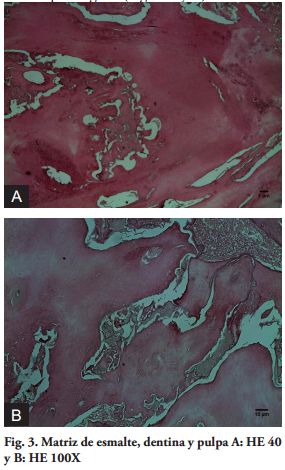

Del punto de vista histológico el OCp presenta una cápsula fibrosa de tejido conectivo rodeando los dentículos, conformados en su interior por tejido pulpar, rodeado de dentina primaria o inmadura, esmalte parcialmente desmineralizado y cemento primario.

El OCj, presenta una cápsula externa de tejido conectivo fibroso y el tejido calcificado consiste esencialmente en dentina primaria o inmadura, esmalte en distintos grados de calcificación y cemento inmaduro (9,10).

Al examen histopatológico se observó la presencia de matriz de esmalte, esmalte, dentina y pulpa conformando un odontoma complejo erupcionado de acuerdo a las características clínico-patológicas (Fig. 3 A y B).